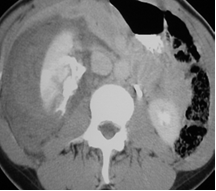

Fractured Kidney with large

retroperitoneal mixed

hematoma-urinoma

Initial image